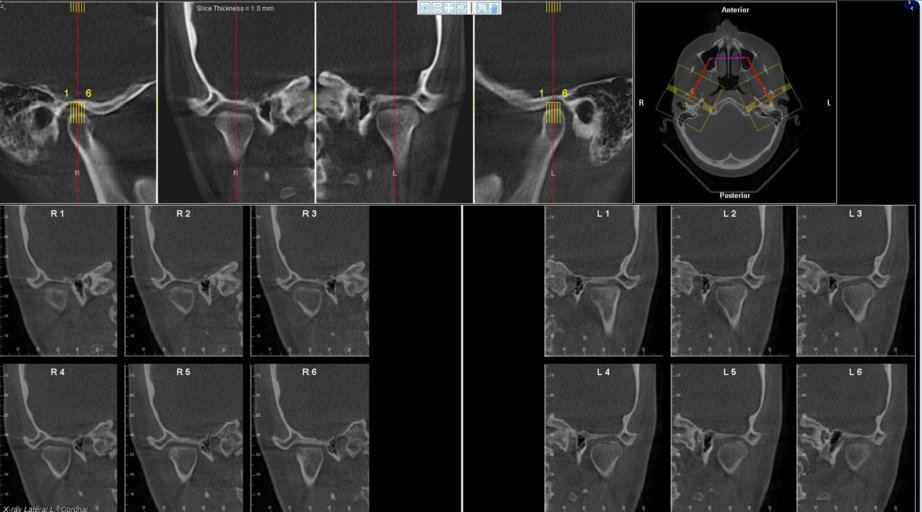

In this image of my condyles, do they appear normal/healthy or is there any bone loss?

Attached is an image of my condyles. Are they normal and healthy or Do you see any bone loss such as flattening or erosion of them? If there does appear to be some bone loss, how does this affect my bite and the appearance/position of my jaw?? Is...